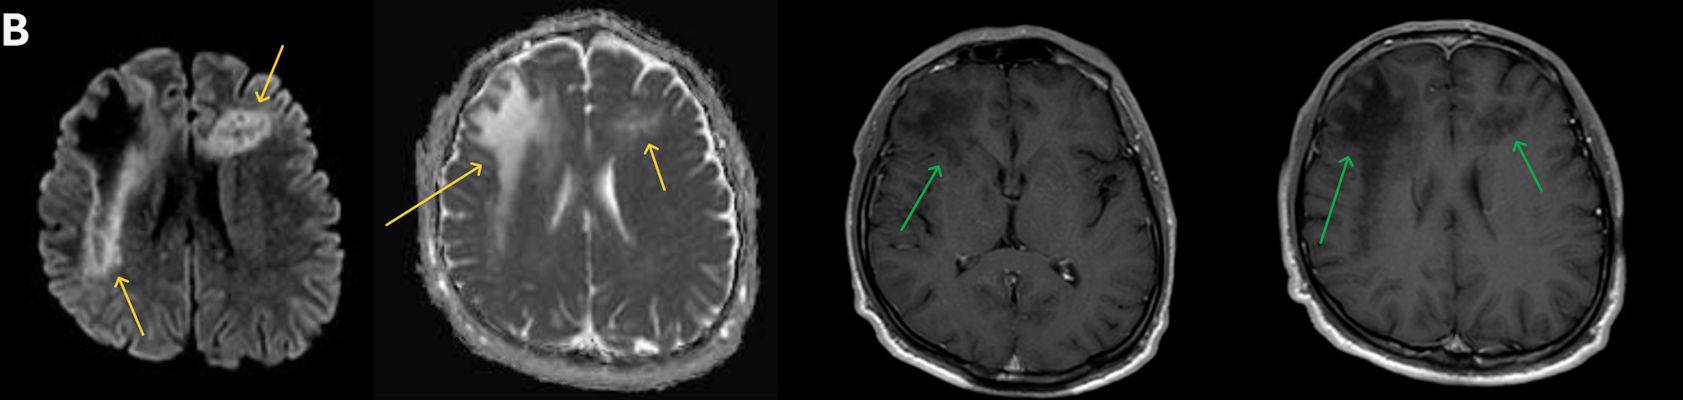

1. A) Aksiyel T2A görüntülerde bilateral sağda belirgin frontoparietal subkortikal ve derin periventriküler beyaz cevherde subkortikal U fiberleri boyunca yerleşimli sinyal artımları (oklar) izlendi.  Tarifli alanlar aksiyel T1A serilerde hipointens görünümde (oklar) izlendi.

2. B) Aksiyel diffüzyon ağırlıklı serilerde bilateral sağda belirgin frontoparietal subkortikal ve derin periventriküler beyaz cevherde periferal DAG hiperintens ADC hipointens, hafif diffüzyon kısıtlaması (oklar) eşlik etmektedir. IVKM sonrası kesitlerde tarifli alanlarda belirgin kontrast tutulumu (oklar) izlenmedi.